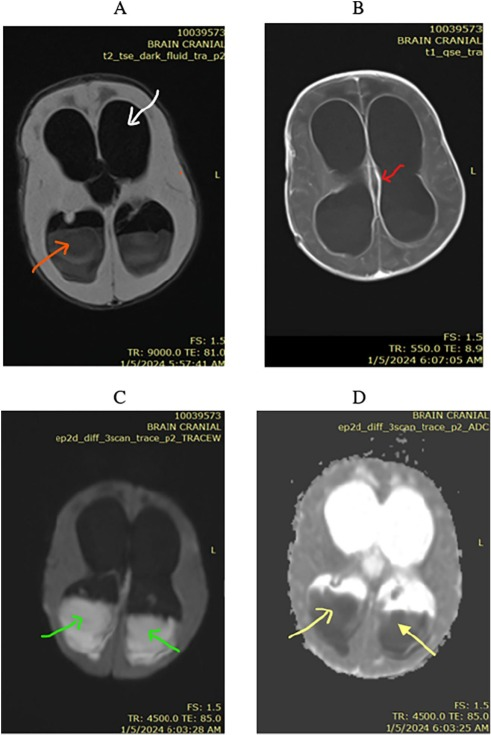

💡Intraventricular empyema🧠 • FLAIR – intraventricular hyperintense material • Post-contrast T1 – ependymal enhancement (ventriculitis) • DWI – marked hyperintensity • ADC – low signal (restricted diffusion) https://t.co/oBc7jB9a5K

1

26

141